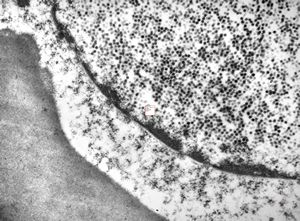

M, 28y. | leishmaniosis … skin of the cheek